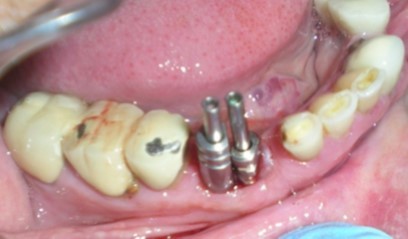

Unplanned implant placement or change in angulations of the implants due to anatomic limitations3,4 such as mandibular canal, mental foramen, nasal floor, sinus cavities or roots of the adjacent teeth, might result in close approximation of the implants (Figure 1), which poses tough challenges to the restorative dentist, who have to overcome certain technical difficulties for the fabrication of the prosthesis including making of a proper impression.

Figure 1.Radiograph – closely positioned implants.

Radiograph – closely positioned implants.